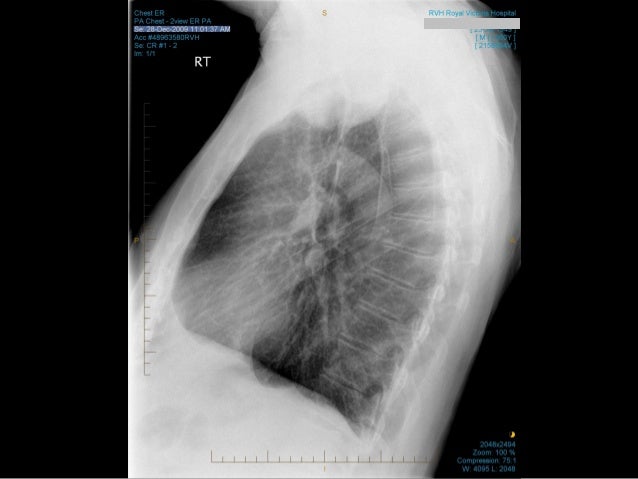

Non-small Cell Lung Cancer Presenting As A Bilateral ...

Herein, we demonstrate a case of a non-small cell lung cancer presenting as bilateral BP. Case Report A 54-year-old man with severe pain and weakness in his neck, shoulders and arms was referred to our institution pain in neck and shoulder, weakness of shoulder girdle ... View Doc